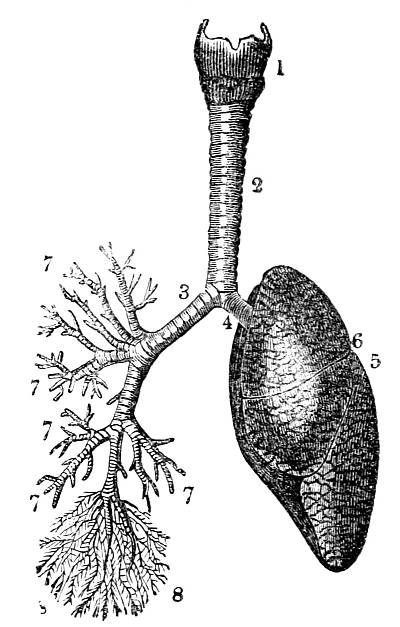

Fig. CXXXV.—

View of the Air Tubes and Lung.

1. The larynx. 2. Trachea. 3. Right bronchus. 4.

Left bronchus. 5. Left lung; the fissures denoted by the

two lines which meet at 6, dividing it into three lobes,

and the smaller lines on its surface marking the division of

the lobes into lobules. 7. Large bronchial tubes. 8. Minute

bronchial tubes terminating in the air cells or vesicles.